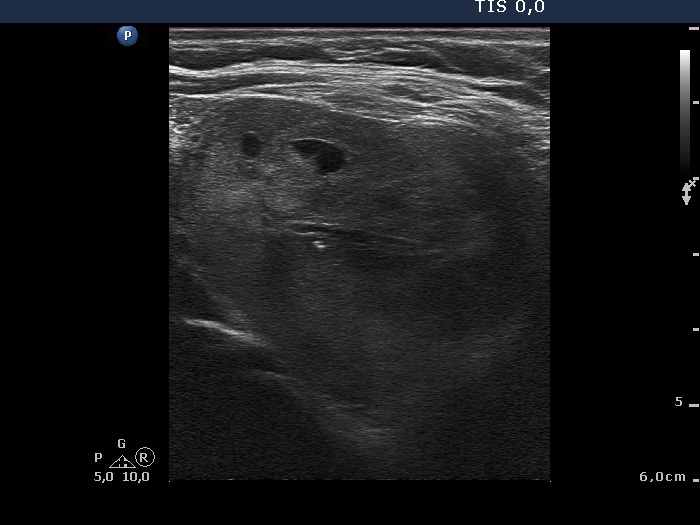

Ultrasonography: a moderately hypoechogenic nodule in the right lobe. Neither halo sign nor perinodular blood flow was present. The dimensions of the nodule were 35x31x37 mm.Cytological picture of the nodule in the right lobe: no colloid in the background. Thyrocytes are arranged in monolayered sheets and in papillary structures composed of microfollicles. Follicular cells are of even size. A few intranuclear holes are present, but these are only projections of vacuoles seen in other parts of the smear, as well. There is no significant atypia.

Ultrasonography: the nodule in the right lobe significantly increased in size. The presence of a halo and a type 2 vascular pattern were doubtful. The dimensions of the nodule were 42x38x49 mm which were significantly greater than those on previous investigation. There was a small hypoechogenic lesion in the left lobe.